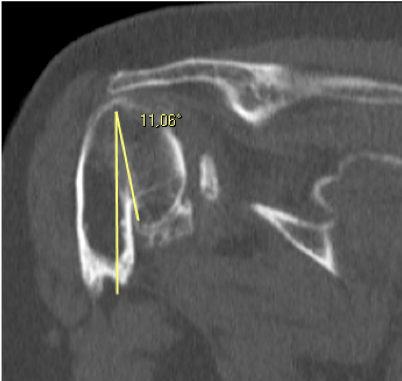

Pre-op

- Sequelae of proximal humerus fracture, treated with plate and screws in 2001

- New right shoulder fracture, treated conservatively in 2008